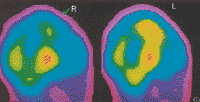

脑血流(CBF)减少是新生儿缺氧缺血性脑病(HIE)的重要原因之一。头颅CT检查可显示HIE患儿脑部的组织形态学变化,SPECT脑血流灌注显像能反映正常新生儿和HIE患儿脑CBF的情况[1-3] 。为了解HIE患儿脑部组织形态学变化与CBF的关系,对35例HIE患儿进行SPECT脑血流灌注显像和CT检查,并作对比分析,现报道如下。

2.方法。SPECT脑血流灌注断层显像按本院常规[2,3] ,检查日龄(7±4)d ......